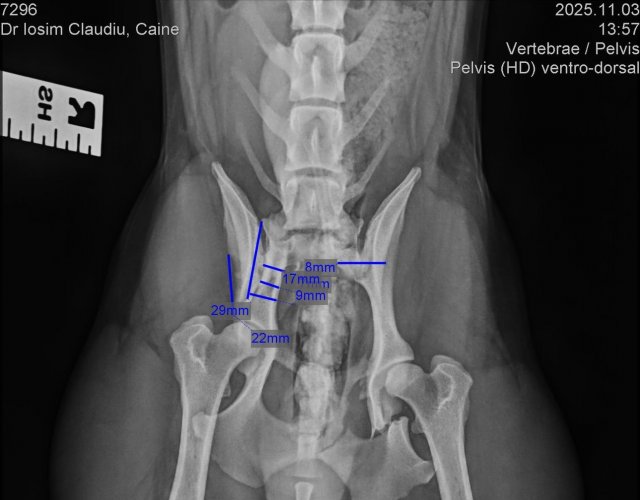

Caine accidentat

O doamna a gasit un caine lovit de masina si l-a tras pe marginea drumului pentru a suna peste tot in cautare de ajutor. Am raspuns pozitiv si am facut totul pentru el. Din pacate nu a putut fi salvat, decedand a doua zi dupa interventia chirurgicala. Foarte probabil din cauza unei embolii pulmonare. Le multumim celor care au donat. Medicul a anulat factura iar banii vor ajuta desigur alte animale de care ne ocupam zilnic.